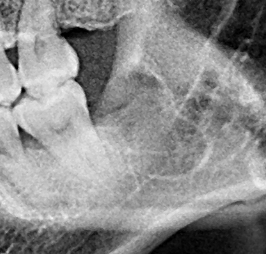

(兩條紅線中間黑色區域即為神經管)

外面拔完時常術後唇麻舌麻,本院發生趨近於零